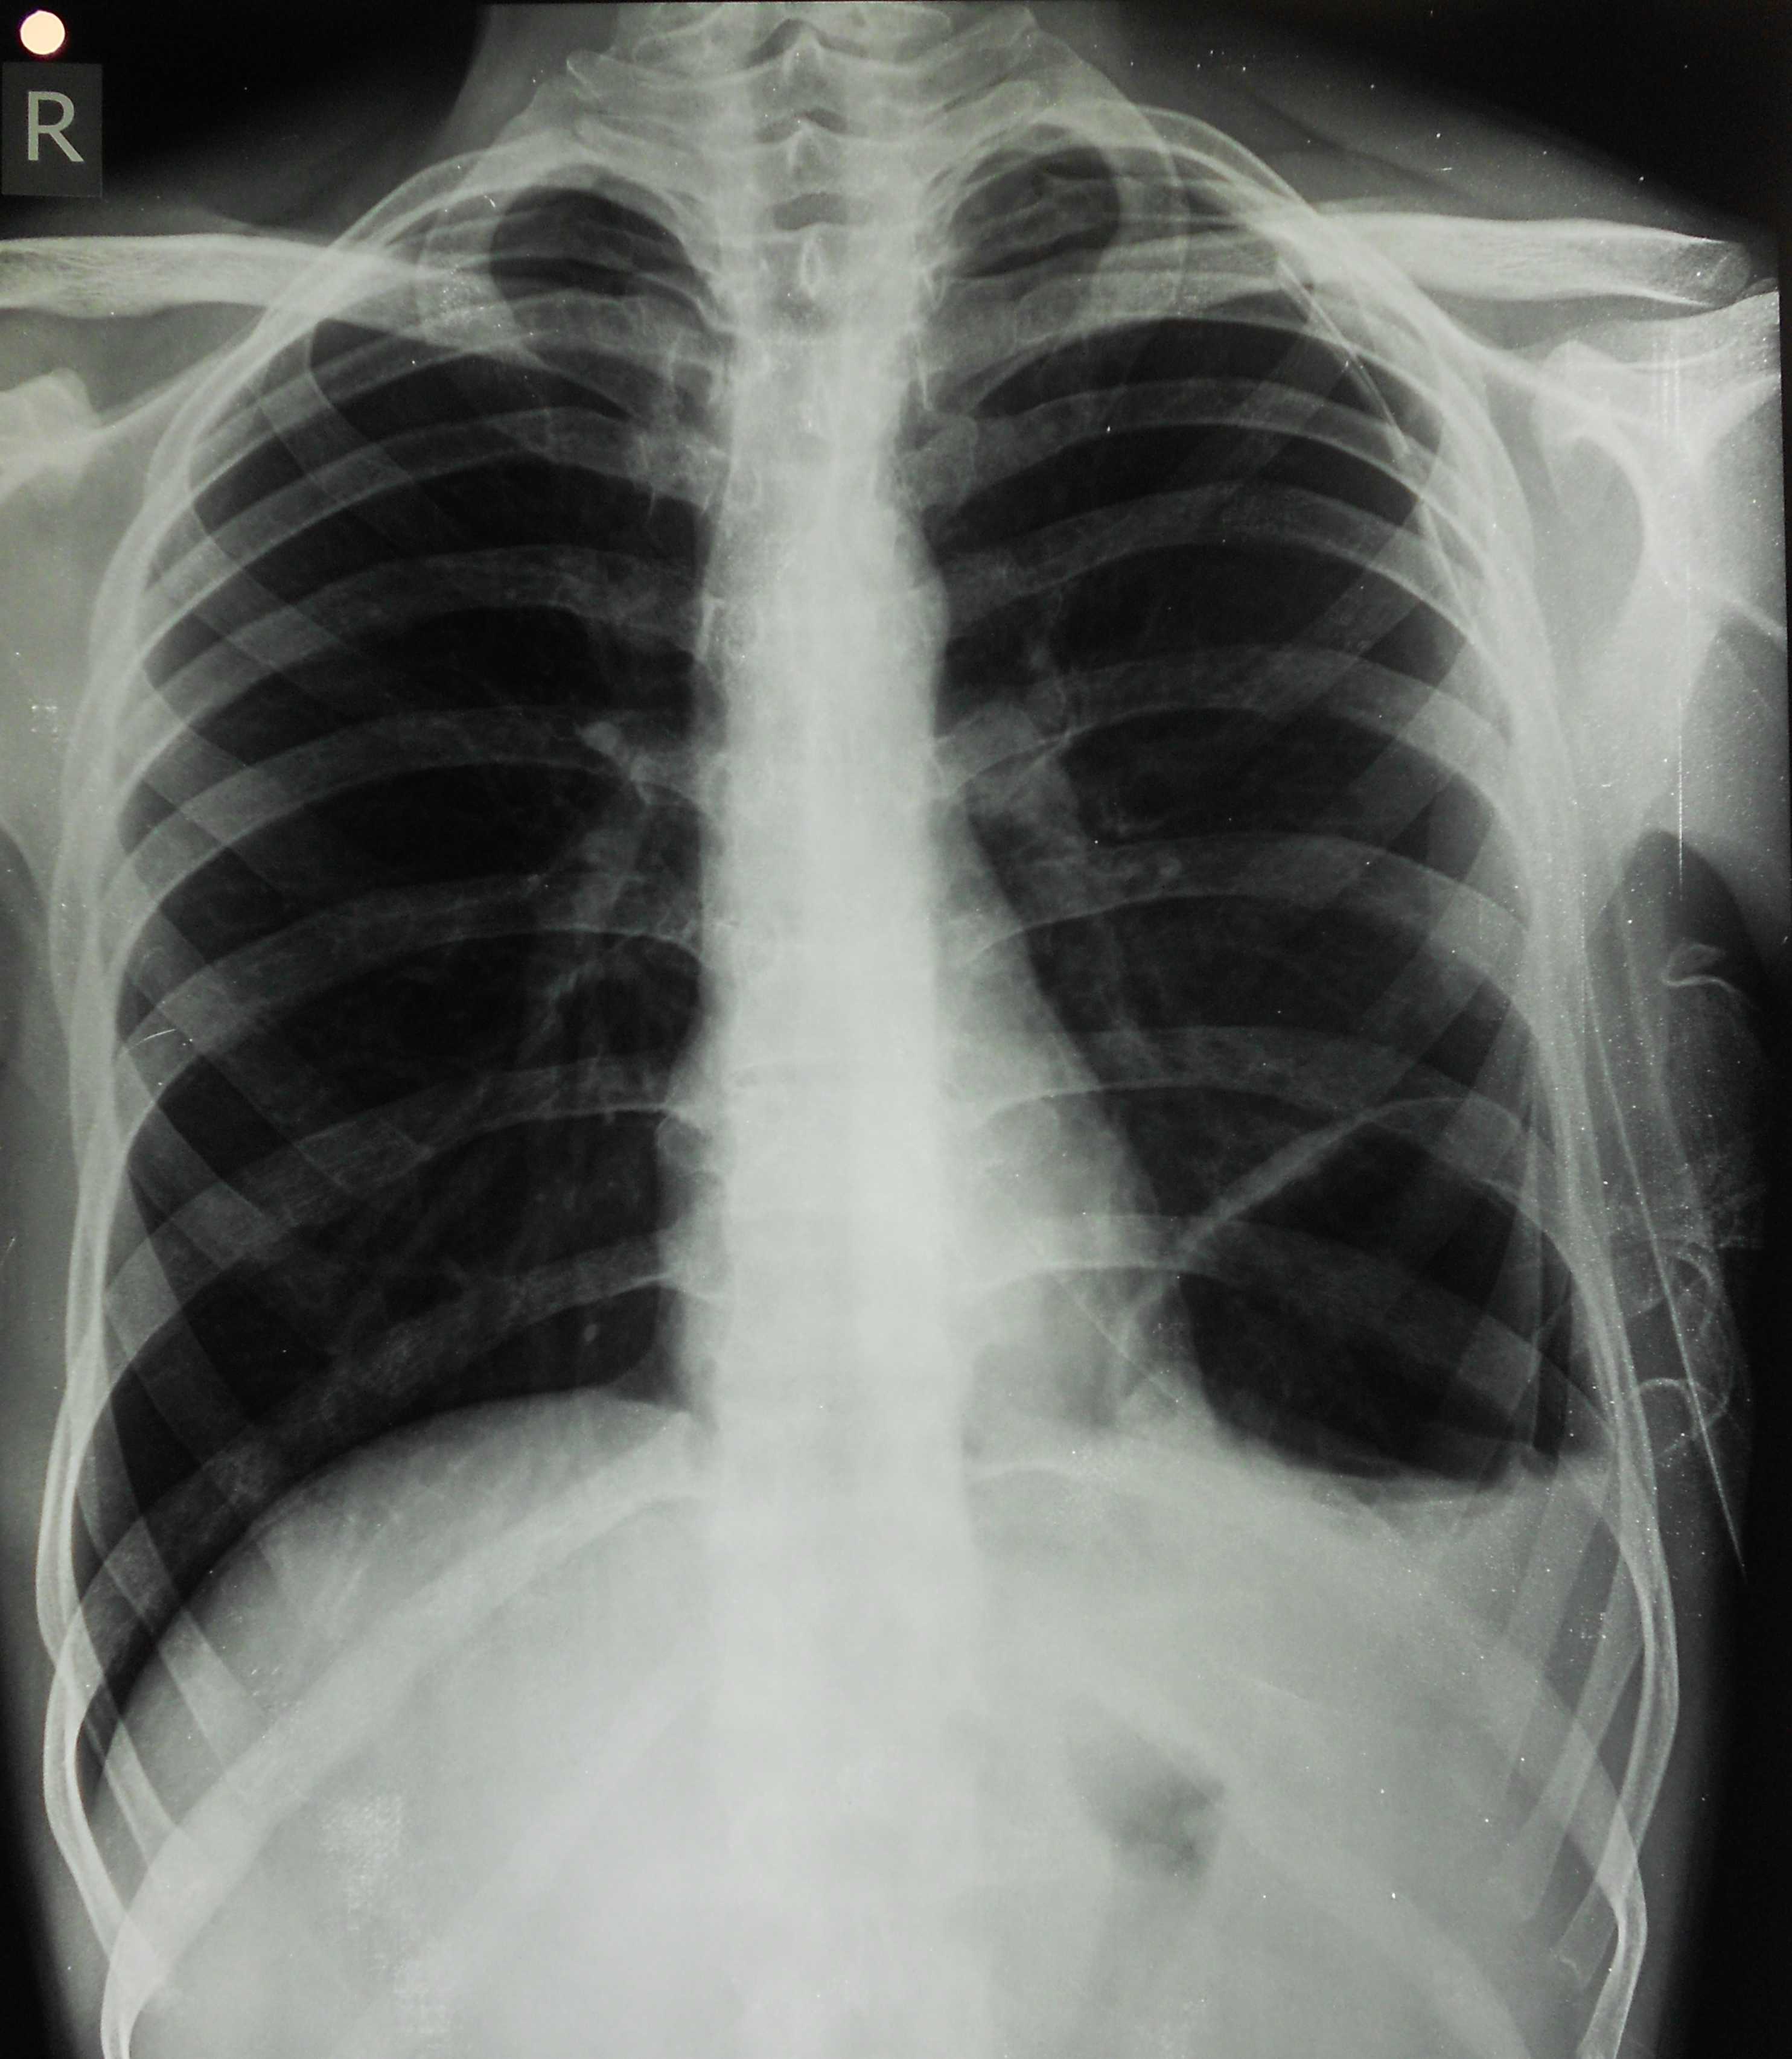

There was persistent and significant air-leak in the ICDs which prevented the left lung expansion. A bronchoscopy was done. The segments of the left lung were blocked one by one with bronchoscopic balloon checking for reduction in air-leak each time. Air-leak significantly reduced on blocking the lateral division of apical segment of left lower lobe. 2 mL of cyanoacrylate glue was injected into the sub-segment. However the air-leak persisted even after the procedure. In the meanwhile, patient again developed fever (1010F) and abdominal pain two days after repeat ERCP (POD-14). A USG abdomen was done which revealed significant collection in epigastrium, right subhepatic space, and between bowel loops. He was managed conservatively for 2 days but when the fever did not subside and collection did not resolve (as confirmed on repeat USG); consultation taken from interventional radiologist who did percutaneous catheter drainage of septated right hepatic collection. Approximately 80 mL of thick pus was drained. The epigastric collection was relatively anechoic and 30 mL of bile aspirated from that side. Both were sent for culture-sensitivity which revealed Candida tropicalis sensitive to amphotericin B which was started immediately. Patient fever was settled after catheter drainage of collection. He was well for 4 days after this procedure (POD-20). Air-leak in the ICD also started decreasing. Once the percutaneous catheter and abdominal drain output became nil, a repeat USG abdomen was done which showed significantly reduced collections. Both the abdominal drains were subsequently removed. Patient was well for 3 days thereafter (POD-23) and allowed liquids and soft diet. On POD-27, patient started having pain abdomen and distension. X-ray abdomen revealed multiple air-fluid level suggestive of acute intestinal obstruction (Figure 5). A CECT of chest and abdomen were done, left lung was found to have expanded significantly and there was minimal hydropneumothorax whereas abdomen revealed grossly dilated small bowel and large bowel loops with a pelvic collection. He was then taken up for exploratory laparotomy on POD-29.

Figure 5 Multiple fluid-air levels with biliary stents in situ.